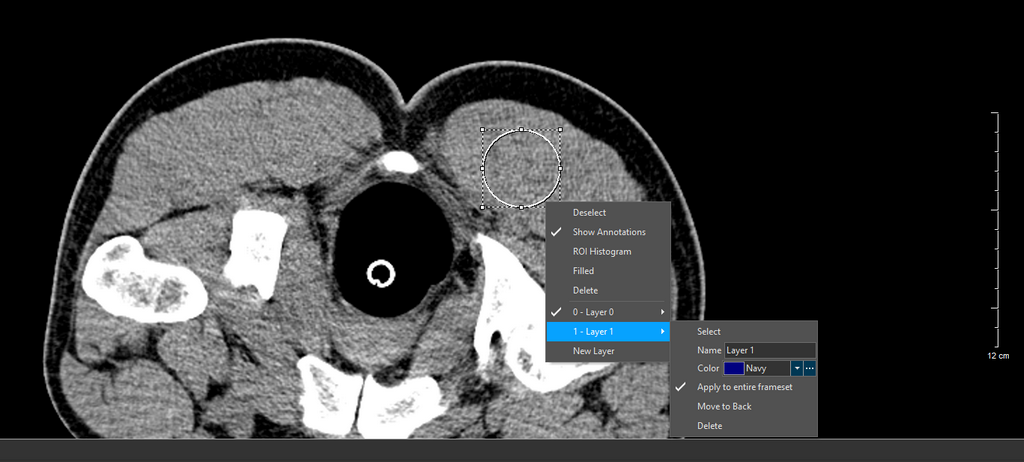

The ROI right-click menu is shown.

After the image is highlighted, right-click to display the Annotations menu. This consists of Deselect, Show Annotations, ROI Histograms, Filled, Delete, and Layers. Any number of layers can be added. You can also choose to apply a Annotation Layer to an entire Frameset by selecting the option Apply to entire frameset. Note that this option may not be applicable for Key Objects as Key Objects may contain different framesets.

By default, the Layer 0 is selected. A Layer can be deleted by selecting the Layer and clicking the Delete option.